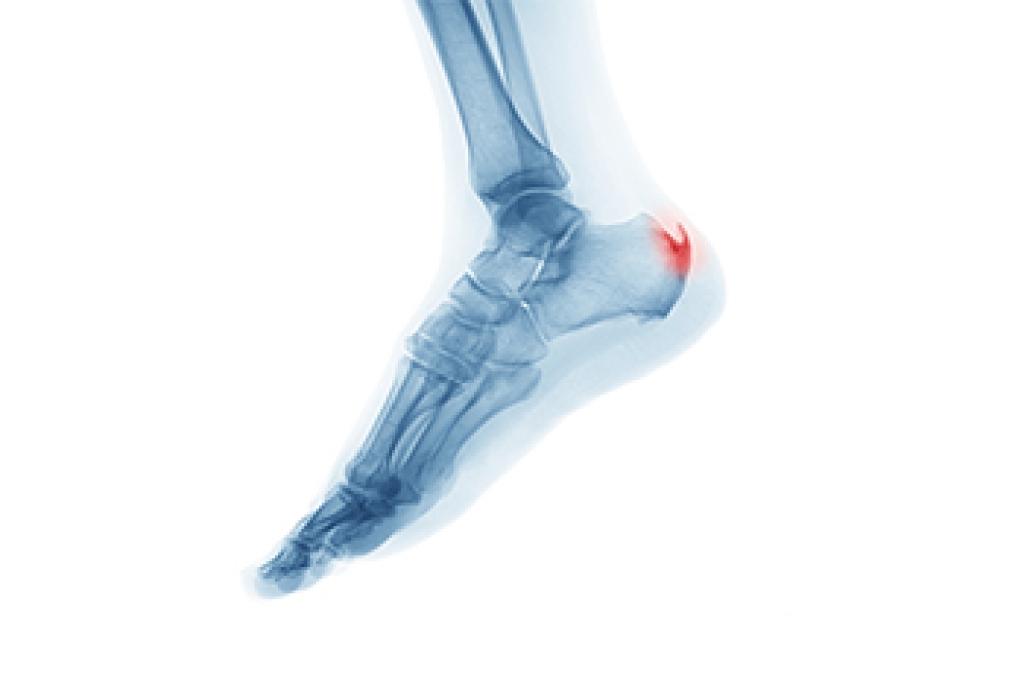

Tarsal tunnel syndrome, which can also be called tibial nerve dysfunction, is an uncommon condition of misfiring peripheral nerves in the foot. The tibial nerve is the peripheral nerve in the leg responsible for sensation and movement of the foot and calf muscles. In tarsal tunnel syndrome, the tibial nerve is damaged, causing problems with movement and feeling in the foot of the affected leg.

- Involves pressure or an injury, direct pressure on the tibial nerve for an extended period of time, sometimes caused by other body structures close by or near the knee.

A physical exam of the leg can help identify the presence of tarsal tunnel syndrome. Medical tests, such as a nerve biopsy, are also used to diagnose the condition. Patients may receive physical therapy and prescriptive medication. In extreme cases, some may require surgery.